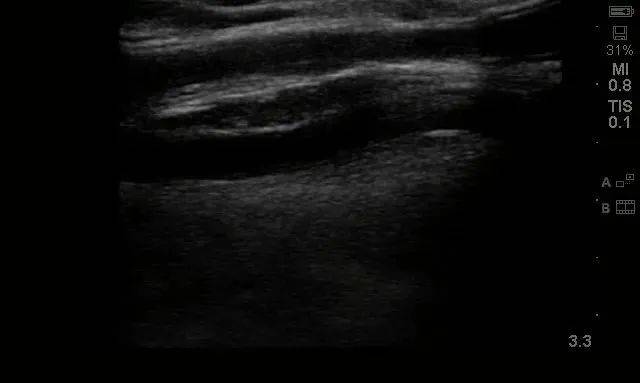

患者来院后 , 医生为其查体 , 左上臂为人工血管动静脉内瘘术后 , 触诊可及“U”型人工血管内瘘成条索状 , 质硬 , 无法触及震颤及听及血管杂音 , 考虑人工血管动静脉内瘘急性闭塞 。 而急诊彩超也提示:人工血管内充满血栓 , 无血流 , 同时合并回流贵要静脉狭窄(图1、图2) , 遂收住院拟行动静脉内瘘经皮球囊扩张血管成形术+血栓取栓术 。

图1:术前彩超报告

图2:术前回流贵要静脉-人工血管吻合口处狭窄并血栓形成